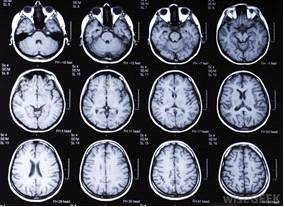

Магнитно-резонансная томография

(МРТ) - это метод получения изображений,

индуцированных сигналом ядерного магнитного резонанса. Принципиальным отличием

МРТ от КТ является то, что при МРТ измеряемой величиной является

намагниченность ядер определенного типа, находящихся в выделенном элементе

объема, в то время как при КТ - коэффициент поглощения рентгеновского излучения

различными биологическими тканями. Клиническое применение метода МРТ

заключается в изучении пространственного распределения ядер водорода, фосфора и

некоторых других элементов в теле человека. Основной величиной, регистрируемой

в МР-исследовании, является отклик магнитных ядер на воздействие переменного

магнитного поля, который зависит от плотности ядер и других параметров,

специфичных для каждого участка тела.

Преимущества МРТ: метод позволяет достигать

исключительно высокого контрастирования тканей, получать в ходе одного

исследования изображение во всех анатомических проекциях, изучать динамические

процессы, связанные с движением биологических жидкостей (крови, ликвора, мочи,

желчи), а также, благодаря применению контрастных веществ, с высокой точностью

различать перитуморальный отек и собственно опухоль. К недостаткам МРТ следует

отнести довольно высокую (не только в Украине, но и во всем мире) стоимость

исследования, а также невозможность его проведения при наличии у пациента

ферромагнитных имплантатов.

Среди множества клинических приложений метода

МРС наибольшее число относится к исследованию пациентов с опухолями головного

мозга.